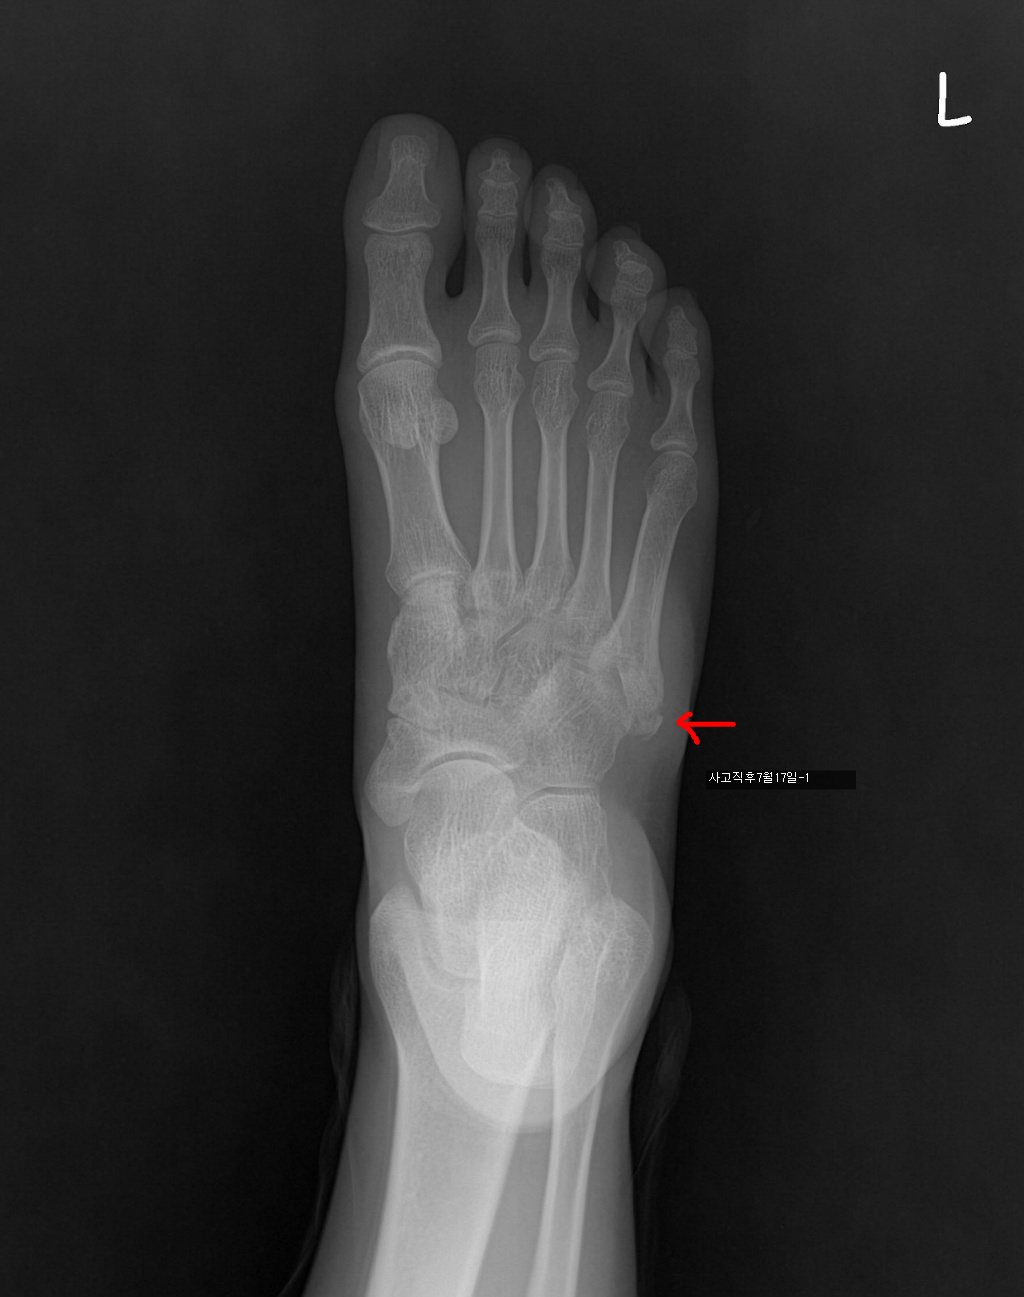

7/17 : 출근 중 지하철 계단에서 구르는 사고로 좌측제5중족골기저부 골절

7/18 : 관헐적 정복 및 금속내고정술  시행 및 반깁스 (2주)

아래는 그간의 사진입니다. 제 눈은로는 수술직후의 사진과 3개월후의 사진의 차이를 잘 모르겠네요..